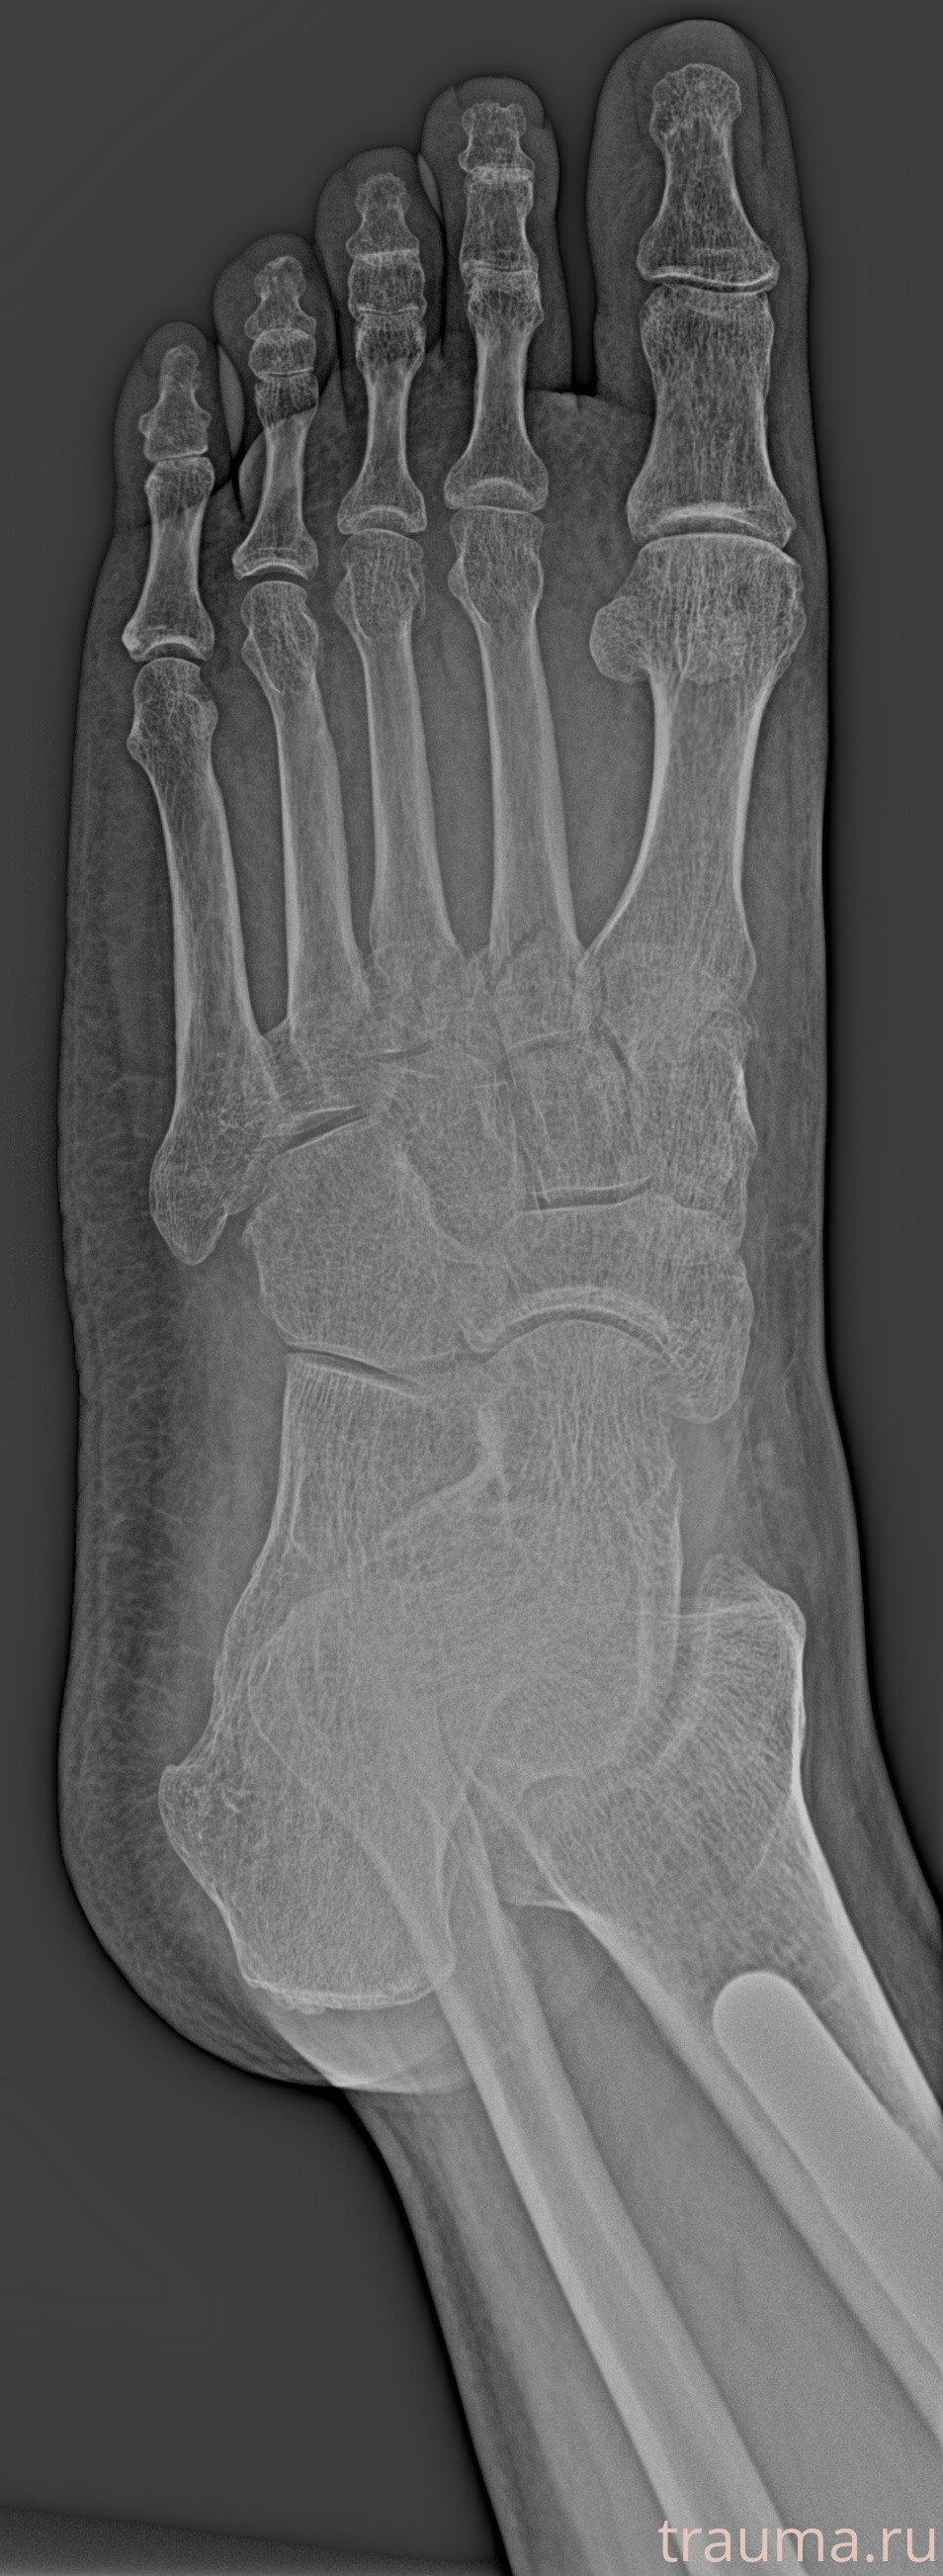

Рентген на дому: по вашему адресу приезжает врач-рентгенолог, травматолог-ортопед с мобильным рентгеновским аппаратом, проводит диагностику травмы или заболевания, делает необходимые рентгенограммы, дает рекомендации по дальнейшему лечению. Получить качественные снимки в домашних условиях возможно благодаря уникальной методике, разработанной МосРентген Центром для института  Склифосовского